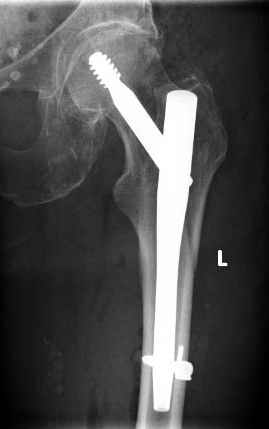

Поступила пациентка 75 лет с пертрохантерным переломом левой бедренной кости. 15 лет назад перелом справа, который прооперировали тогда гвоздем лециуса.

Я его только в книжках видел. Сейчас остеосинтез гамма-нагелем справа. Пациентка стала примером прогресса медицины. Век живи, век учись...Вальдемар Киндсватер.